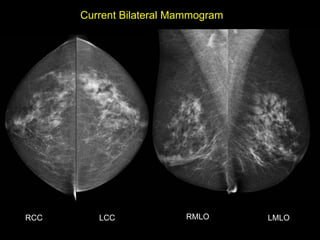

Current Bilateral Mammogram

RCC      LCC             RMLO       LMLO

HISTORY โ€ข 65 yofemale โ€ข Presents from OSH with worsening โ€žleft breast swellingโ€Ÿ for 8-9 months โ€ข New 1 month history of โ€žchange in left nippleโ€Ÿ

• 15.

• 16.

Current and ComparisonLeft Breast MGs 4 YRS PRIOR CURRENT 4 YRS PRIOR

• 17.

US retroareolar region US Left upper outer breast

• 21.

Grade 2 InvasiveLobular Carcinoma with LN positive for Metastatic Adenocarcinoma SURGERY โ€“ Mastectomy with LN dissection

Invasive Lobular Carcinoma โ€ข10-15% of all invasive breast ca โ€ข Sensitivity of MG 57-81% โ€“ Mass most common โ€“ usually spiculated (44- 65%) โ€“ Distortion 10-34% โ€“ Asymmetry 1-14% โ€ข Much less freq assoc with calcs than IDC โ€ข Sensitivity of US 68-98% โ€“ Spiculated mass โ€“ Shadowing Lopez et al. Radiographics 2009; 29:165.